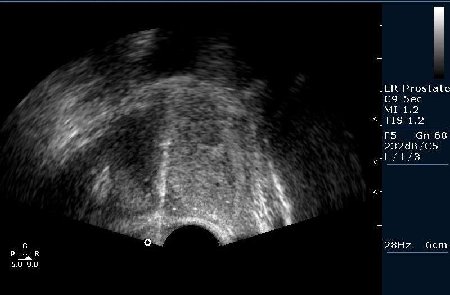

Биопсия предстательной железы под контролем Ультразвуковой визуализации. Рутинная практика в нашем отделении pадиологии, выполняется практически всем пациентам с повышенным уровнем ПСА (естественно, учитывая результаты осмотра урологов).

Предстательная железа